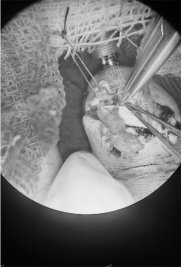

4:30,手术准时开始,术式为左小指清创再植及血管移植术。在高倍显微镜下,医生们凭借精湛的技术和丰富的经验,小心翼翼地对断指进行清创,精准无误地吻合血管、神经和肌腱。每一个动作都精准到位,每一次操作都关乎着手术的成败和小星未来的生活质量。经过长达2个半小时的不懈努力,手术顺利完成,术后一次通血成功,小星的断指暂时被成功“接”了回去。

果然,7月9日早上,小星左小指再植术后出现血管危象。这一突发状况让整个医疗团队再次进入紧张状态,医院迅速做出反应,立即将小星再次安排到手术室,展开左小指血管危象探查修复术。

从11:00到13:30,医生们在手术台上争分夺秒,凭借高超的医术和冷静的判断,成功解决了血管危象问题。术后,小星返回病房,医护人员继续密切观察血运,将患肢抬高并保持功能位,确保伤口敷料干洁。在医护人员的精心照料下,小星的血运情况逐渐好转,再植指体最终成活,家长携患儿顺利出院。